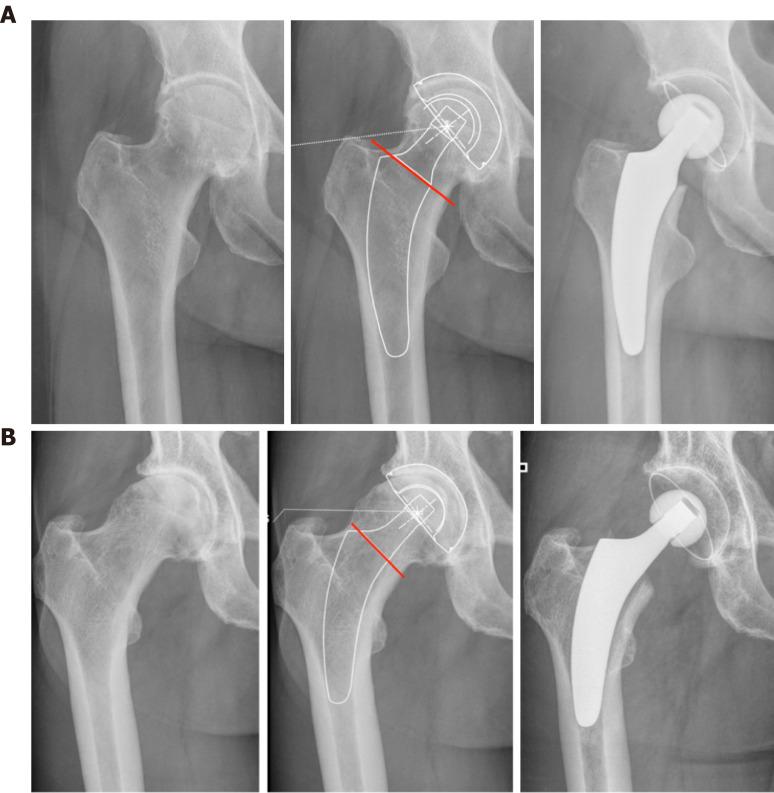

Short stems in total hip arthroplasty (THA) are becoming increasingly popular. In Germany, already 10.4% of all primary THAs are performed using a cementless short stem. The concept of modern, calcar-guided, short stems aims for an individualized reconstruction of the hip anatomy by following the calcar of the femoral neck, a bone- and soft-tissue-sparing implantation technique, and physiological loading. The stem design uses either metaphyseal fixation alone or additional diaphyseal anchoring, depending on the stem alignment and indication. These individualized anchorage types increase the potential indications for the safe use of a short stem. The design features may account for potential advantages of current short stem implants compared with earlier short-stem designs, particularly in cases of reduced bone quality or osteonecrosis of the femoral head and femoral neck fractures. The implantation technique, however, requires distinct knowledge regarding the characteristics of varus and valgus positioning, with the potential for clinical consequences. A learning curve for surgeons new to this technique must be taken into account. Cortical contact with the distal lateral cortex appears to be crucial to provide sufficient primary stability, and the use of intraoperative imaging to identify "undersizing" is highly recommended. Current results of several national registries indicate that calcar-guided short stems are among the most successful implants in terms of mid-term survivorship. However, long-term data remain scarce. This review introduces the characteristics of calcar-guided short-stem THA and summarizes the current evidence.